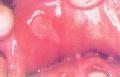

| [ 口腔溃疡 ] |  | 更多>> |